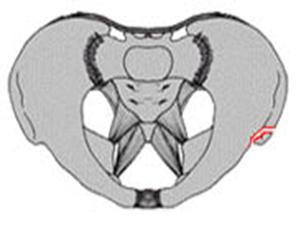

Compresie laterala

Fracturi pelviene multiple Fracturi pelviene multiple

Compresie bilaterala Compresie bilateralaAspect CT

Compresie bilaterala Aspect CT Disjunctie sacro-iliaca stanga Compresie antero-posterioara